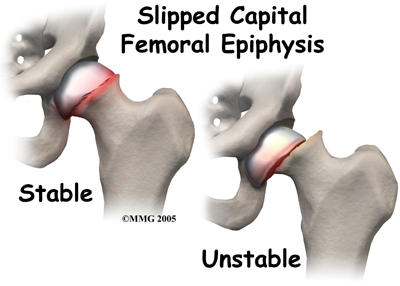

is the slipping of the growth plate of the ball of the hip joint. It usually happens in obese, older children.

Related Document: A Patient's Guide to Slipped Capital Femoral Epiphysis

In the case of slipped capital femoral epiphysis, surgery is often required. The femur can be pinned through the skin (percutaneous pinning). The surgeon may need to open the joint to place pins in it. Sometimes the hip that is not affected is also pinned because it is also likely to slip.